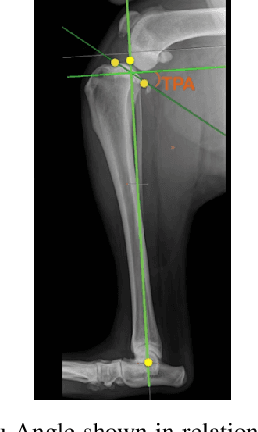

Abstract:Stifle joint issues are a major cause of lameness in dogs and it can be a significant marker for various forms of diseases or injuries. A known Tibial Plateau Angle (TPA) helps in the reduction of the diagnosis time of the cause. With the state of the art object detection algorithm YOLO, and its variants, this paper delves into identifying joints, their centroids and other regions of interest to draw multiple line axes and finally calculating the TPA. The methods investigated predicts successfully the TPA within the normal range for 80 percent of the images.